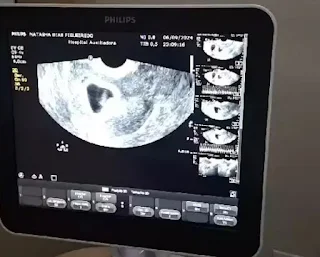

| Ultrassom mostrou a surpresa aos pais: quatro bebês. (Foto: Arquivo Pessoal) |

Durante o ultrassom, o profissional pensou que eram

trigêmeos, mas quando seguiu analisando o exame, notou que eram quatro novos

filhos.

Quando ele continuou fazendo o ultrassom e disse que, na verdade, eram

quadrigêmeos, não acreditei. Ele mostrou que todos estavam com o coraçãozinho

batendo e aí liguei para o meu esposo”.